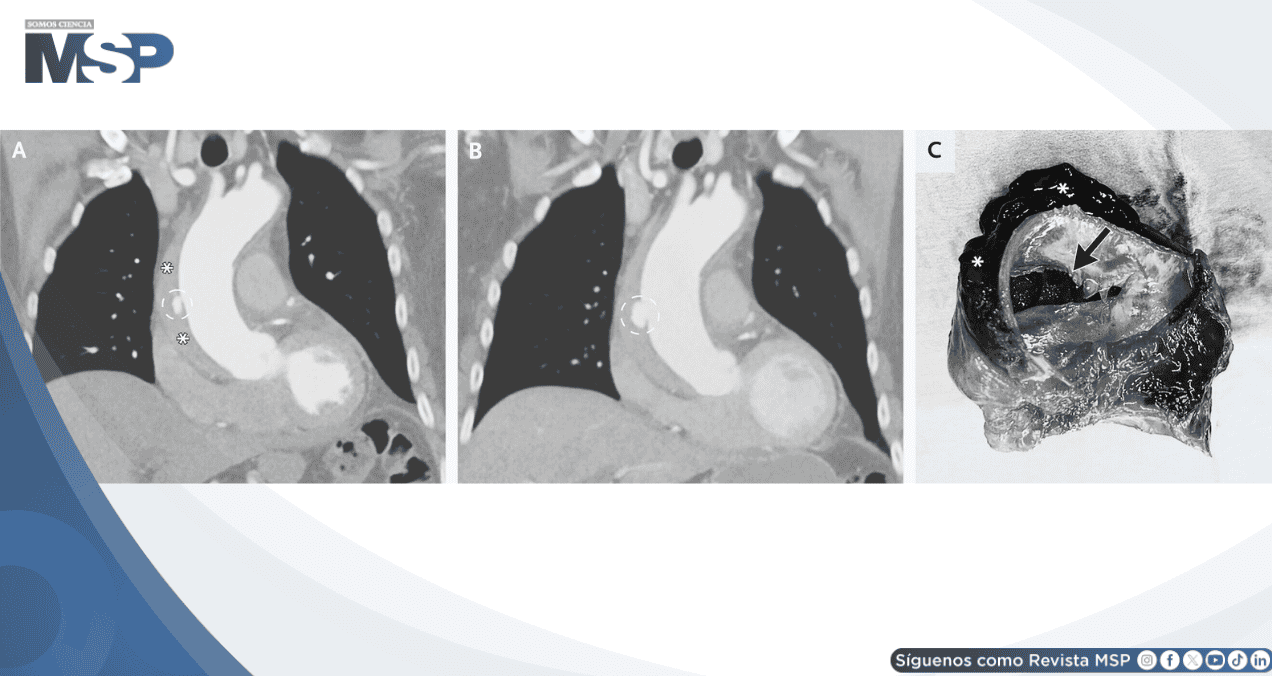

La TC evidenció una proyección ulcerada en la aorta torácica ascendente, asociada a un hematoma intramural que se extendía hacia el arco aórtico y la porción proximal de la aorta descendente.

Tres días después, una TC de control mostró aumento del tamaño de la proyección ulcerada. Se realizó entonces una sustitución abierta supracoronaria de la aorta ascendente y del hemiarco. Durante el procedimiento se identificaron un desgarro intimal y una disección de la aorta ascendente, además del hematoma intramural.